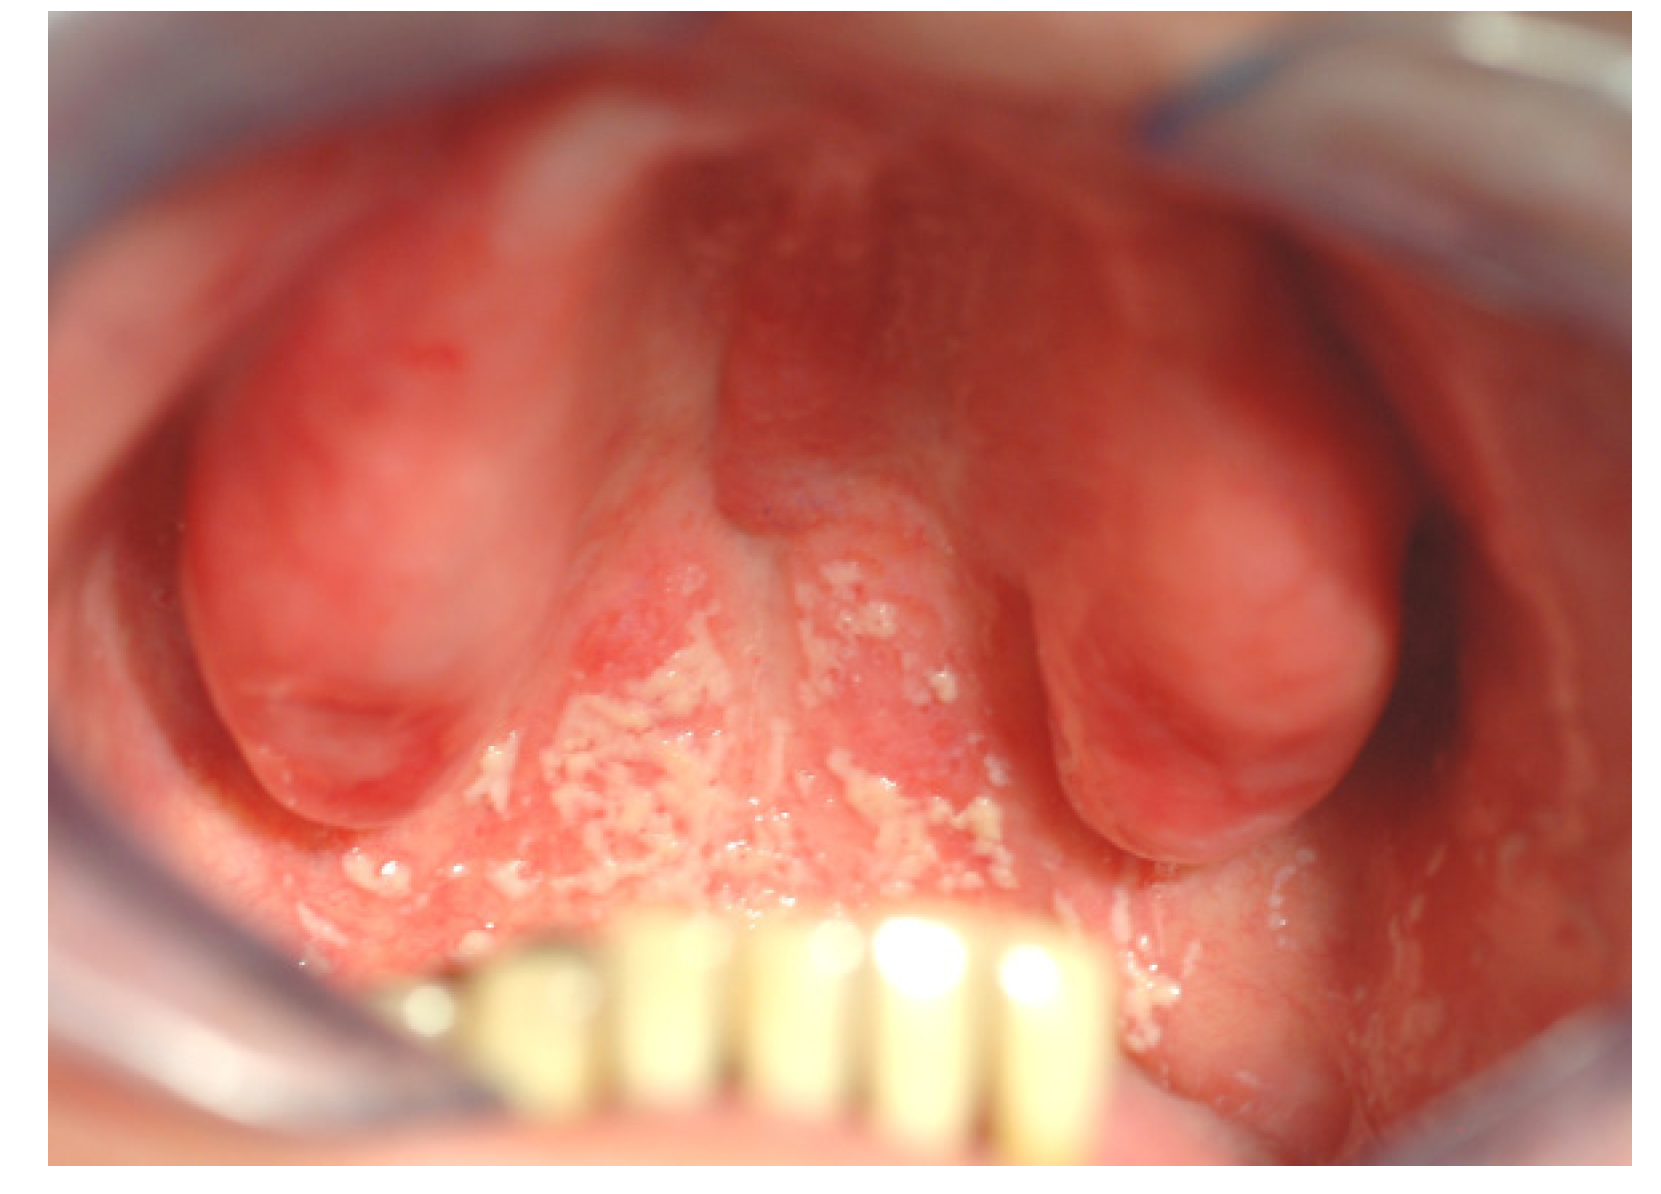

Oral infections can affect the hosts’ general health in many ways [8,22]. Firstly, it is unfavorable to have ongoing infections in general. Oral infections such as gingivitis can involve quite large areas, and is a constant burden for the hosts’ immune system. This is, of course, most harmful for patients with other ongoing inflammations or diseases. Secondly, oral microbes may spread to other organs within the host either via the respiratory system or through the blood stream [1,2,8,20,22,23]. This is, again, most harmful for patients with other complications, such as artificial heart valves, or transplanted organs. Elderly people with pneumonia will often have oral microbes in their lungs, which may have been aspired from the oropharynx and caused the inflammation in the lungs [8,20,23]. The direct causality between oral infections and systemic disease has been difficult to prove. It is difficult to detect whether the oral microorganisms were present prior to the disease and were the direct cause of the infection or not. It is also possible that the oral microbes entered the loci after the primary inflammation occurred due to reduced effect in the immune response system. Candida albicans can spread directly from the oral cavity to the throat and stomach (Figure 2) [24,25]. General candida infections are extremely difficult to cure due to the high risk of re-colonization. Thirdly, individuals with poor general health will normally also have poor oral health, due to malfunctioning immune system and altered chemical and physical conditions in the body, such as reduced saliva flow, iron deficiency, malnutrition, medical treatment, etc. [26,27]. Sick and elderly have reduced ability to clean their teeth properly and are therefore more exposed to development of unfavorable biofilm and subsequent general infection [28].

Figure 2. Patient with denture stomatitis. The infection has spread from the denture covered palate to the throat and stomach. The patient experienced no oral pain and was unaware of the situation (photo: Marit Øilo).